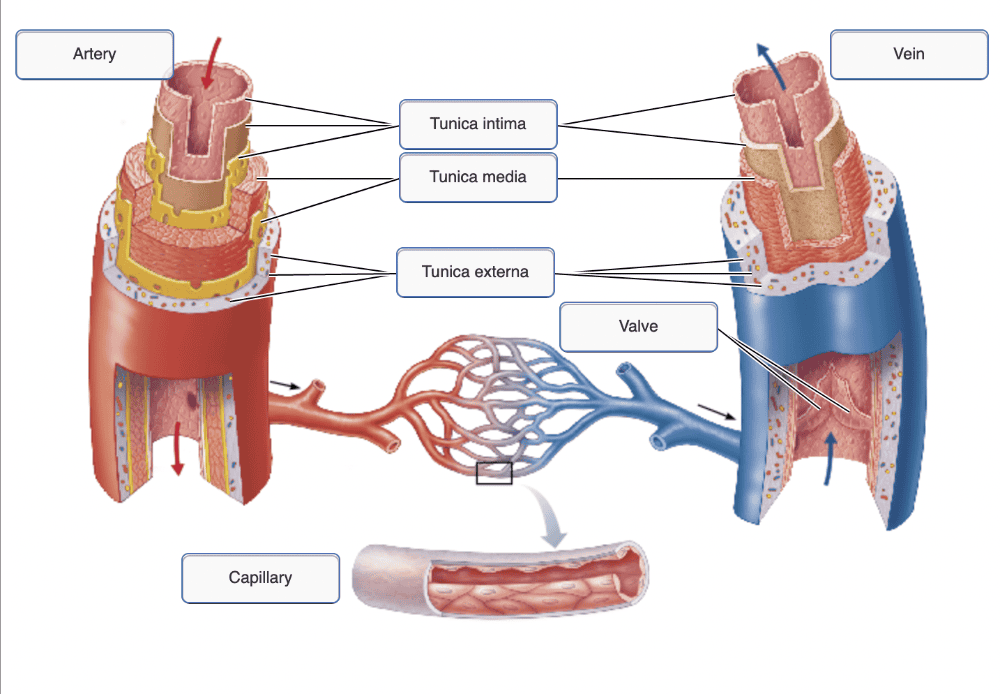

Drag the appropriate labels to their respective targets.

Drag the appropriate labels to their respective targets.